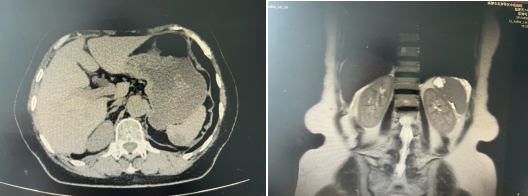

【学科技术】创新手术助力患者康复 —— 我院成功实施首例“腹腔镜脾部分切除术+胆囊切除术”